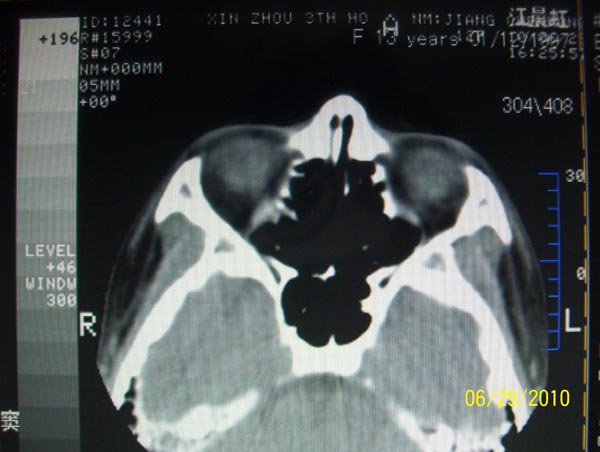

以下是引用随光逐影在2010-6-29 22:28:00的发言:[br]1)右侧下鼻甲肥大(或息肉样变)。2)鼻咽腺样体肥大。

以下是引用随光逐影在2010-6-29 22:28:00的发言:[br]1)右侧下鼻甲肥大(或息肉样变)。2)鼻咽腺样体肥大。

以下是引用随光逐影在2010-6-29 22:28:00的发言:[br]1)右侧下鼻甲肥大(或息肉样变)。2)鼻咽腺样体肥大。

以下是引用拾荒者在2010-6-30 19:22:00的发言:[br]右侧下鼻甲粘膜肥厚,鼻腔阻塞,鼻旁窦窦腔清晰,支持考虑慢性鼻炎。